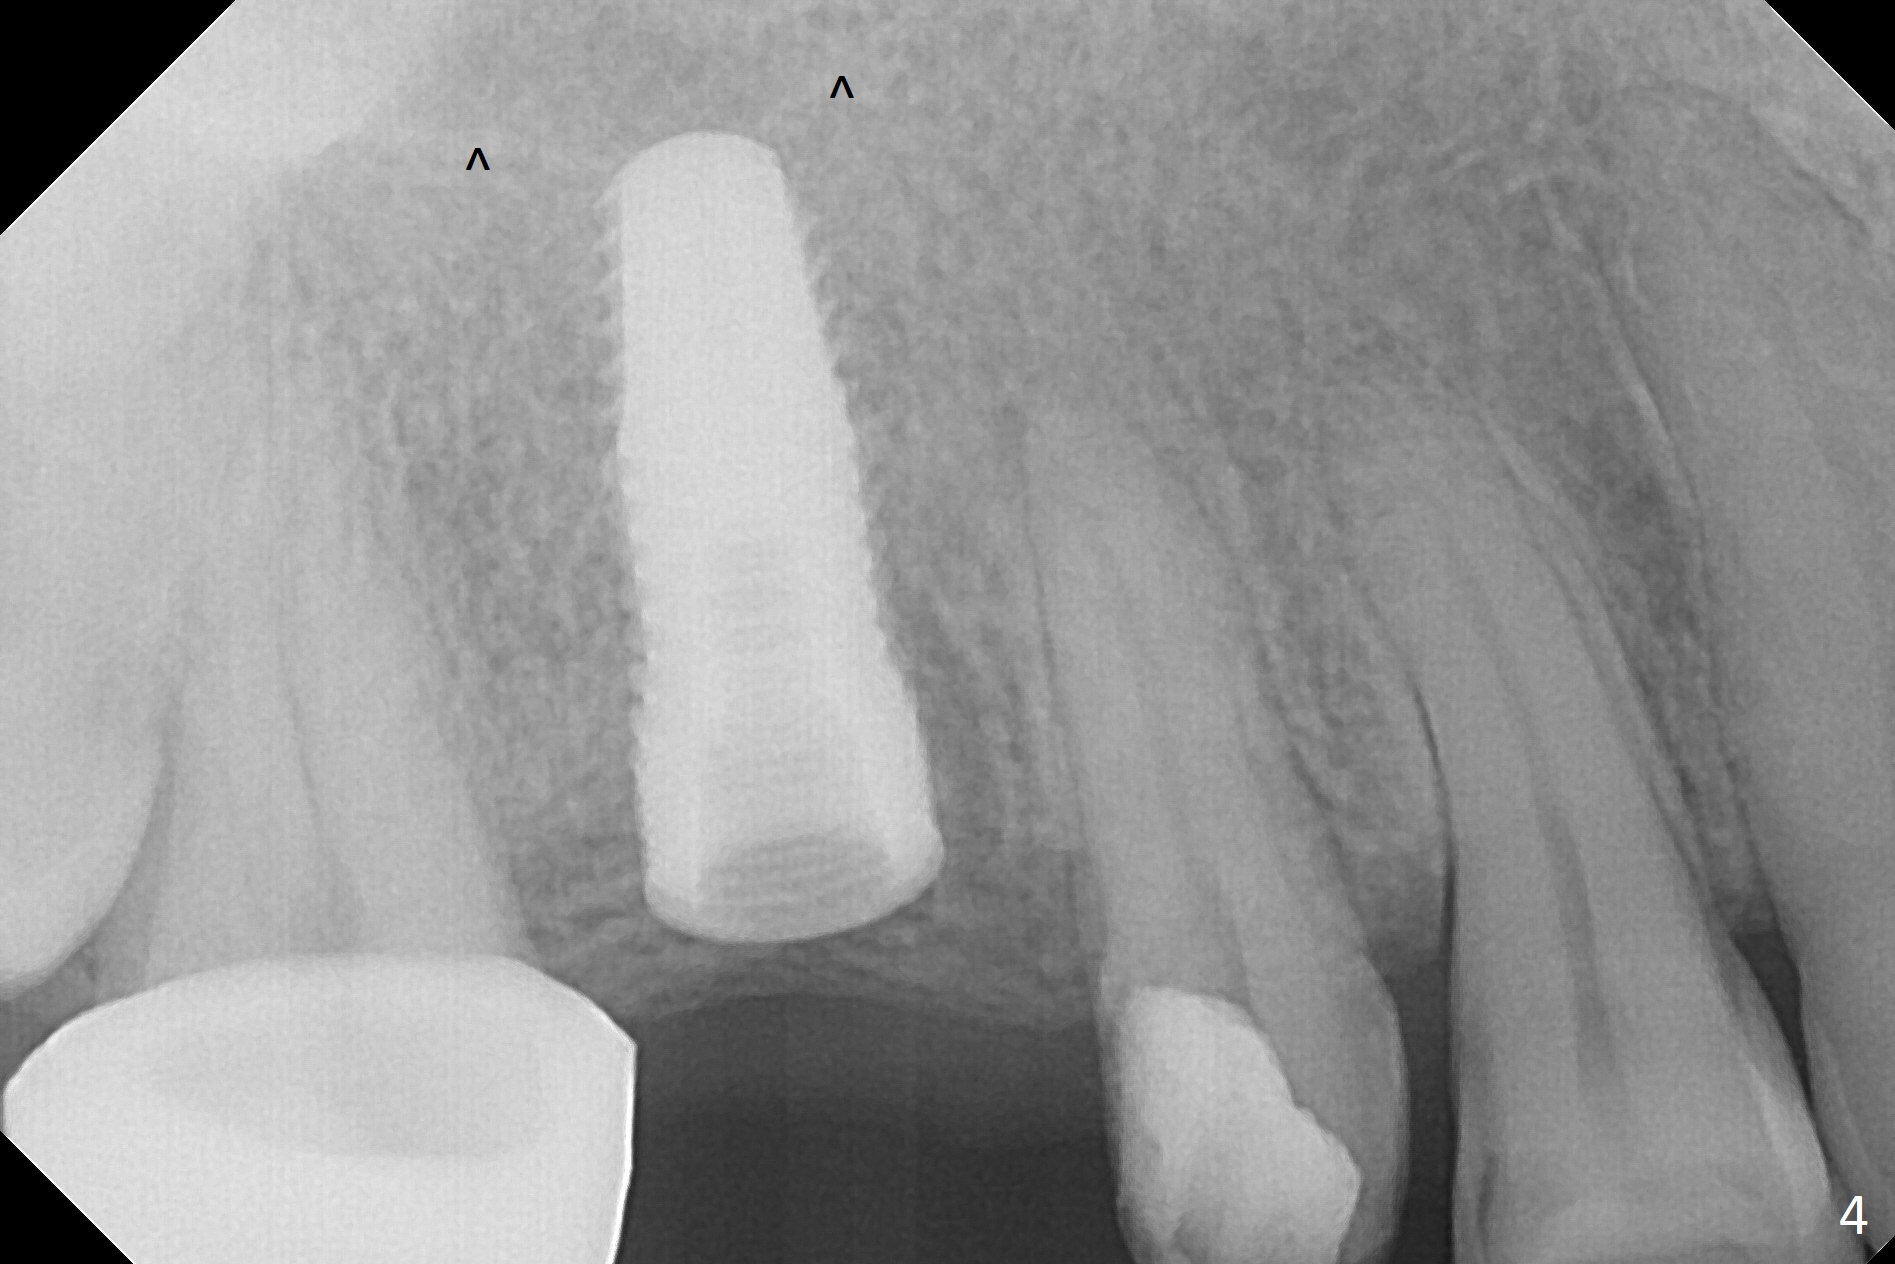

When the bridge is partially removed, the tooth #4 is found to have extensive caries. IRM is placed following carious removal (Fig.1). Magic Split testing shows that the bone density is high (flapless). Osteotomy is initiated by 1.6 mm drill, but the handle of the drill needs to shift mesial (Fig.1 red arrow). When the latter is done, the whole drill (2 mm) needs to move distal (Fig.2 double red arrows). When a 4.5x14 mm drill finishes the osteotomy, it is in the middle of the edentulous space (Fig.3). After use of 5 mm tap, a 5.3x14 mm implant cannot reach the depth (Fig.4,5). Following increase in osteotomy depth from 16 to 18 mm (gingival margin) until 5 mm drill in diameter, the implant placement level is more ideal (Fig.6,7, slightly subcrestal) with insertion torque maintaining at >55 Ncm. The sinus floor (Fig.4 arrowheads) may be penetrated when the osteotomy depth increases (Fig.7 *), but the sinus membrane remains intact.